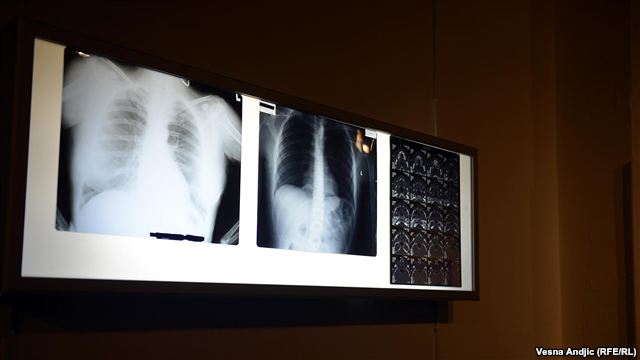

Rendgenski snimci, lekarski nalazi i fotografije povreda postali su deo postavke u okviru izložbe „Muzej nasilja“ koja je u sredu otvorena u galeriji „Podroom“ Kulturnog centra Beograda. Ovaj prostor će na nekoliko nedelja postati javni arhiv medicinske dokumentacije koju su donirale žrtve različitih oblika nasilja – porodičnog, vršnjačkog, institucionalnog ili onog zasnovanog na homofobiji.

“Svi znaju da nasilje šteti generalno ljudima, ali je jači efekat kada vidiš sliku. Ciljali smo dakle na vizuelno i zato i atmosfera jeste malo hororična, da bi ljudi shvatili da je nasilje strašno. Što se mene tiče, možda bi čak bilo bolje da ima još više fotografija – da ljudi baš vide povrede, masnice, otekline koje se ne vide preko X-zraka”, objašnjava Ilićeva.